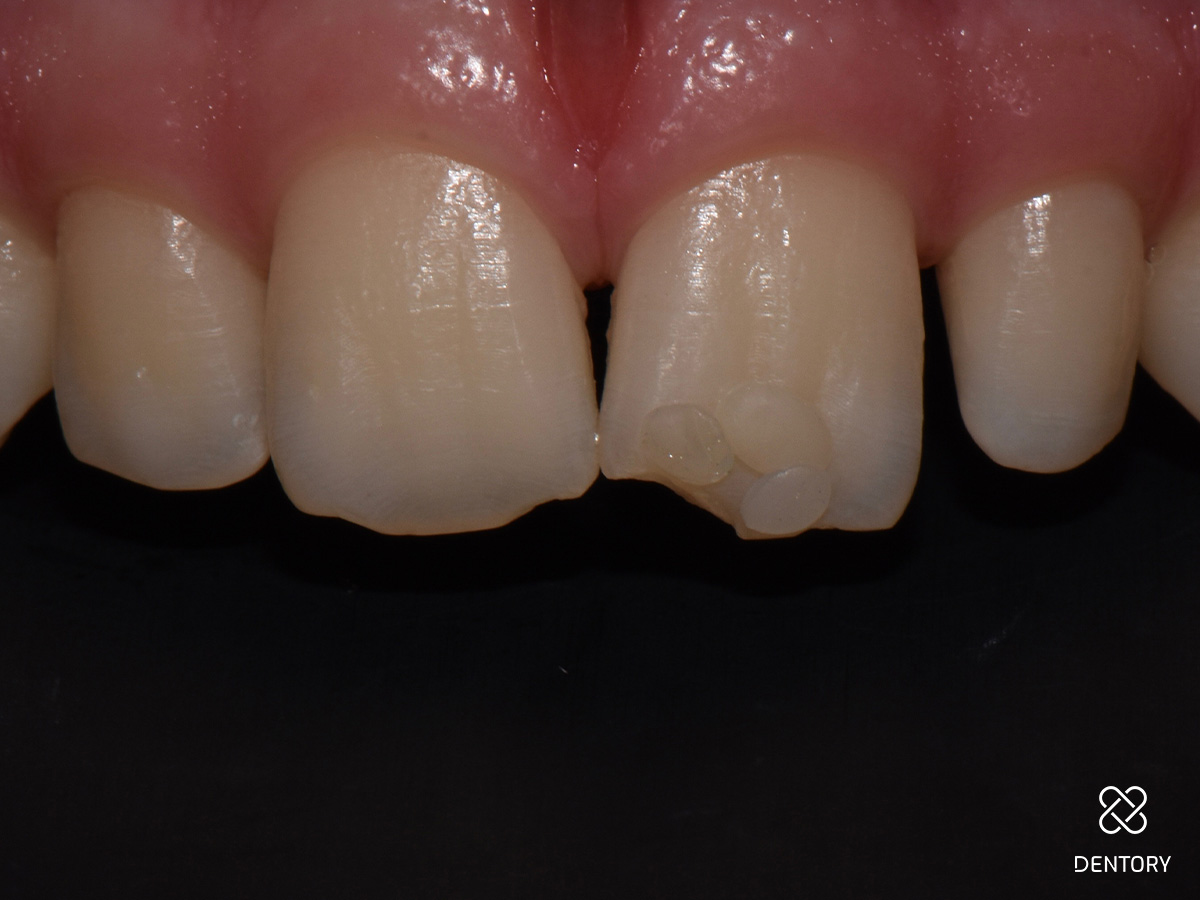

Abbildung 2

Die großzügige Isolierung der Zähne 13-23 mit Kofferdam gewährleistet ein trockenes und störungsfreies Arbeitsumfeld und bietet die Möglichkeit, sich an benachbarten Strukturen zu orientieren.